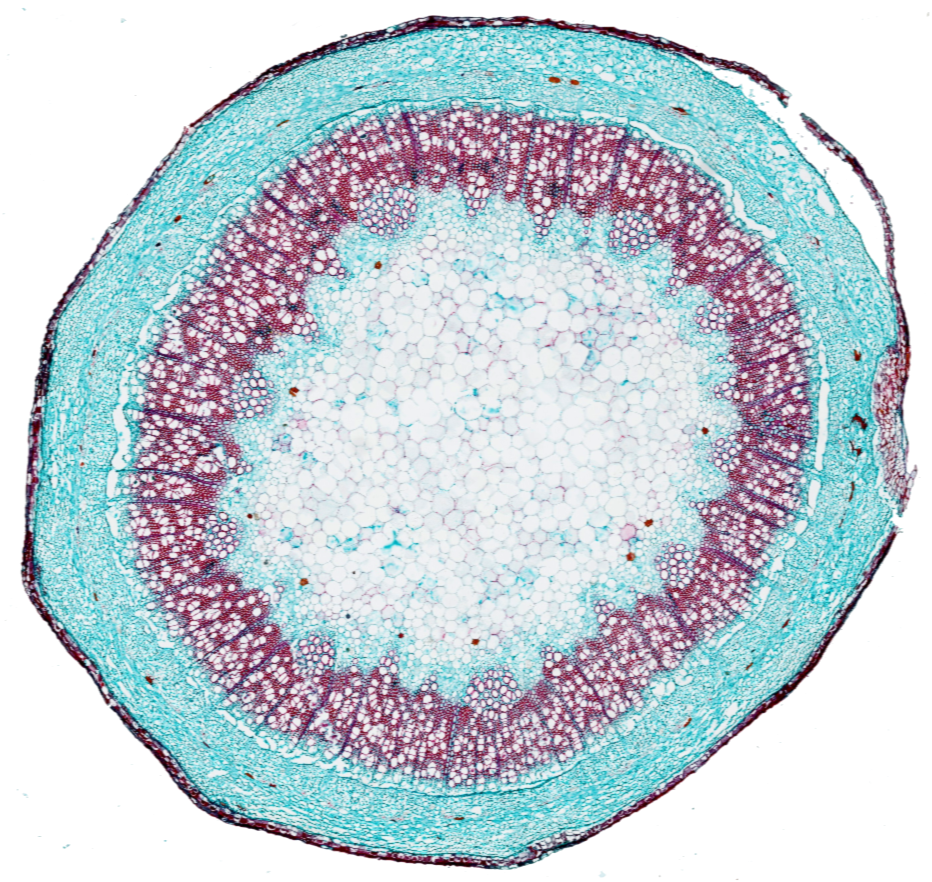

Los escáneres o digitalizadores de láminas son microscopios automatizados capaces de capturar imágenes digitales idealmente en alta resolución a partir de láminas histológicas físicas. Existen distintos modelos según el volumen y la aplicación clínica, pero para diagnóstico deben cumplir estándares estrictos de calidad y precisión.

Digitalizamos tus láminas y entregamos archivos listos para diagnóstico, revisión o docencia, con imágenes de alta resolución que cumplen estándares internacionales y que pueden ser fácilmente integradas por sistemas LIS.